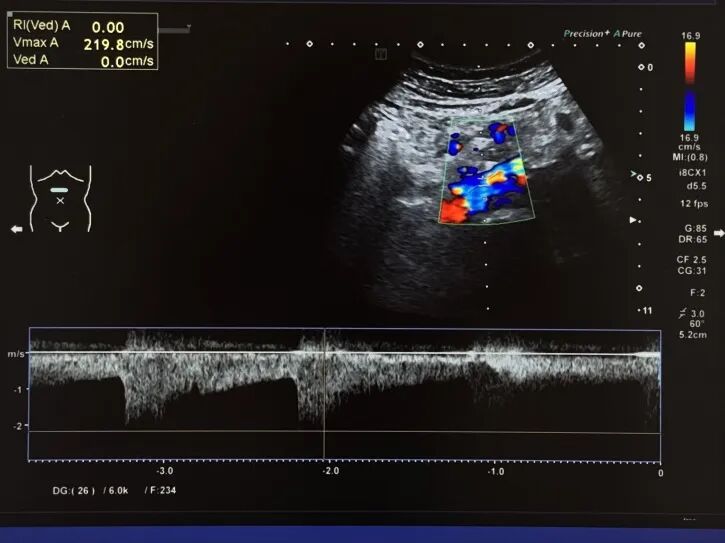

双肾、双侧肾动脉超声提示:右肾大小约9.4*3.2cm,右肾动脉主干狭窄>60%,血流加速,最大流速2.20m/s,RI为0.63。